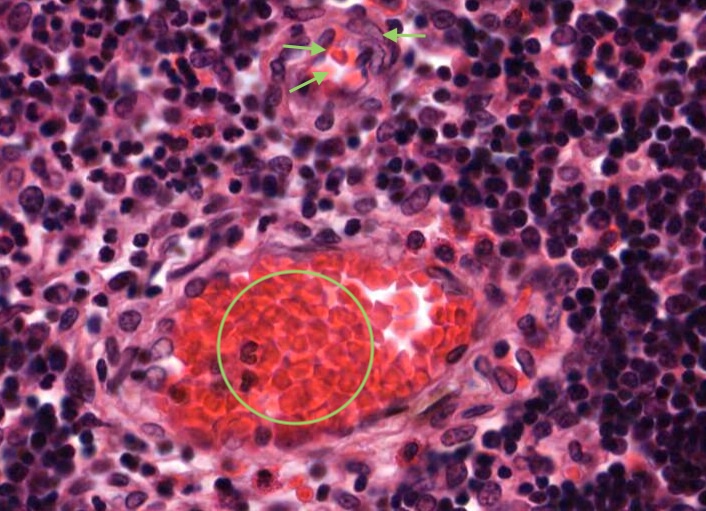

All lymphocytes that enter the cortex of the thymus are not able to contact antigen because of the blood-thymus barrier - it is a physical barrier. The structures that constitute the blood-thymus barrier are endothelium lining the capillary wall (identified by the presence of a few red blood cells) and maybe a pericyte that may be also present, any macrophage in the vicinity/perivascular connective tissue and a type I epithelioreticular cell.

You can see similar components of the blood-thymus barrier around the venule in this image.